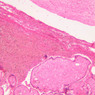

The endometrium of the cervical canal does not slough during the menstrual phase. The glands in this region are relatively large and extensively branched. They are lined by a tall simple columnar epithelium very active in the secretion of mucus. Occasionally these glands become blocked forming Nabothian cysts. The transition of the epithelium of the cervix to that of the vagina is abrupt and is in the region of the external os. At this point, the cervical simple columnar is replaced by the vaginal stratified squamous epithelium (slide B-98 [2.5x-labeled, 10x, 20x, 40x] [2.5x, 10x, 20x, 40x]). This is an area which is commonly inflamed as well as a primary location of cervical cancer.